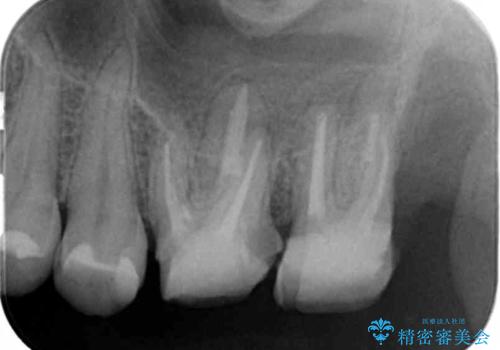

- 半年前から奥歯から嫌な臭いがする、と治療を求めて来院されました。

銀歯を除去したところ、虫歯が大きく再発しこのままではかぶせ直しができないような状況でした。

・深い虫歯 →歯周外科を行うことで歯ぐきの腫れを改善

・根尖性歯周炎 →精密根管治療